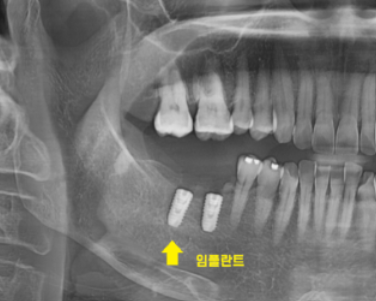

상일동역 치과 수술 직후의 사진입니다.

사진을 보시면 나사가 하나 들어간 것을

확인하실 수 있는데요.

x-ray를 보실까요~?

임플란트가 잘 심어져있습니다.